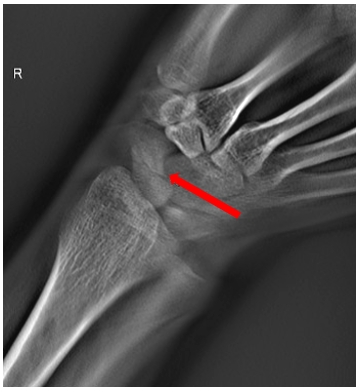

病例二:女,31歲。右手摔傷。

通過斷層融合圖像分析,為豆?fàn)罟枪钦邸?/p>